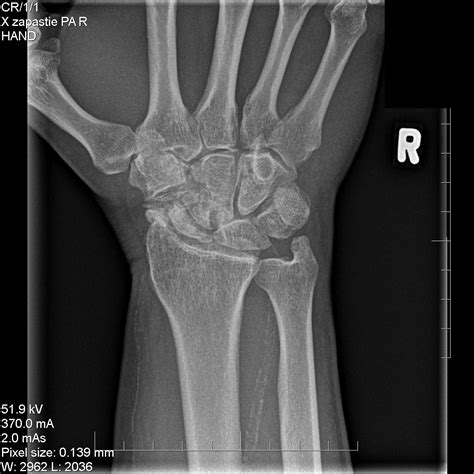

Diagnosing this condition requires a comprehensive physical examination combined with advanced imaging. Physicians typically rely on standard X-rays, which often reveal the characteristic gap in the scaphoid and the narrowing of the joint space. In more complex cases, a CT scan or MRI may be ordered to assess the exact degree of cartilage degradation and to plan potential surgical interventions.

• scaphoid nonunion advanced collapse radiology